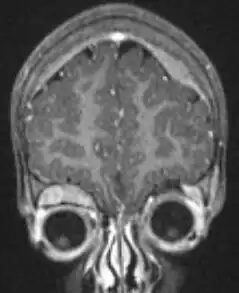

MRI showing orbital and skull vault metastatic NB in 2-year-old